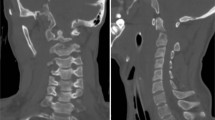

A 6-week-old female Simmental calf was found in lateral recumbency (igloo system, housed with one other calf). The non-ambulatory and recumbent calf was pre-treated by the referring veterinarian with metamizole and then referred to the Clinic for Ruminants for further evaluation. The physical and laboratory examinations (CBC, serum biochemistry profile and blood gases) showed no clinically relevant abnormalities. On neurological examination, the calf appeared conscious and responsive to stimuli but presented in lateral recumbency with non-ambulatory tetraparesis (minimal voluntary movements of all four limbs were preserved). Cranial nerve function was normal. With support, the calf could be raised but showed reduced to absent postural reactions in all limbs. Spinal reflexes were all normal, with increased muscle tone. Conscious pain perception was evaluated to be preserved. Pronounced upper cervical hyperaesthesia with intermittent opisthotonus was evident on neck palpation. Based on neurological findings, the lesion was localised to the C1-C5 spinal cord segments. Based on the clinical history and the calf’s age, the most likely differentials were considered to be trauma, anomaly or inflammation. Lateral cervical digital radiographs (Axiom Luminos dRF, Siemens Healthcare, Erlangen, Germany KV: 69,8, mAS: 25), identified a fractured odontoid process, which appeared to be still attached to the body of the atlas. However, dorsal dislocation of the C2 vertebral body was obvious (Figure 1). The remaining cervical vertebrae displayed no obvious radiographic abnormalities. Based on the radiographic findings our initial diagnosis was a traumatic odontoid process fracture. Instability and spinal cord compression at the fracture site were highly suspected due to the radiographic findings and neurological presentation. Therefore, surgical decompression, anatomical alignment, and stabilisation were favoured for our calf rather than conservative management (such as neck splinting). Potential surgical stabilisation was planned to be performed in collaboration with our small animal neurosurgeons located at the Clinic for Small Animal Surgery and Reproduction. Although the diagnosis of an odontoid process fracture was already established on radiographs, advanced diagnostic imaging was considered to allow better surgical planning and to screen for other traumatic lesions within the remaining cervical vertebrae (because it is reported that multiple vertebral lesions may occur in 5-10% of small animal trauma patients [19,20]). In addition, the owner requested advanced diagnostic imaging examination prior to a cost-consuming surgery to definitively exclude any concurrent and injury-predisposing congenital abnormality at the atlantooccipital region. In the case of a concurrent congenital atlantooccipital fusion, the calf’s owner would have denied any further treatment due to the condition’s potential heritability and associated limitation of future breeding uses. However, because of rapidly deteriorating neurological signs and respiratory distress during trailer transportation to the advanced diagnostic imaging and surgery sites (both located at the Clinic for Small Animal Surgery and Reproduction), the calf was euthanised. MRI and CT examinations were performed immediately post-mortem for scientific reasons. The MRI examination was performed using a 1.5 T magnetic resonance unit (Magnetom Symphony, Siemens Healthcare, Erlangen, Germany). The dead calf was positioned in sternal recumbency because this allowed positioning with only minor neck manipulation (compared with dorsal recumbency) and hence was assumed to lower the risk of artificial and manipulation-induced fracture dislocation; however, dorsal recumbency would have allowed closer contact between the area of interest and the table coils. T1-weighted (T1W; TR: 768, TE: 13), T2-weighted (T2W; TR: 3980, TE: 109) and short tau inversion recovery (STIR; TR: 5790, TE: 61, TI: 140) pulse sequences of the cervical vertebral column were obtained in the sagittal (T1W, T2W and STIR) and dorsal planes (STIR) with a slice thickness of 3 mm (STIR) and 2.5 mm (T1W and T2W). The MRI examination confirmed severe spinal cord compression at the level of the fracture site due to dorsal displacement of the C2 vertebral body and pronounced vertebral step misalignment (Figure 2). Cranial and caudal to the compression site, the spinal cord appeared swollen and exhibited a hyperintense intramedullary signal on the T2W-images and on the STIR-images, with mixed intensity (but predominantly hypointense appearance) on the T1W-images. Based on signal-pattern spinal cord oedema, intramedullary haemorrhage or myelomalacia were considered as potential differentials. A T2* gradient echo (T2*-GRE) sequence would have been helpful to further characterise this spinal cord T2W-hyperintensity but unfortunately was not performed. Dorsal to the compression site, the paravertebral musculature showed a focal area of T2-hyperintensity (with similar appearance on the STIR-images), which was supposed to be indicative of a dorsal traumatic event at this level. A post-mortem CT examination of the cervical vertebral column was performed with a 64-slice, helical CT scanner (Somatom Definition AS, Siemens Healthcare, Erlangen, Germany). Transverse images of the cervical vertebral column were acquired (64 x 0.6-mm detector collimation, 120 KVp, 120 ma, 1 sec rotation time and 512 x 512 reconstructed image matrix). A bone algorithm (B70s convolution Kernel) was used for reconstruction. CT images reflected MRI findings and furthermore identified the fracture site at the synchondrosis between the body of the axis and the odontoid process (Figure 3). The fracture line was directed in a dorsoventral oblique direction from the dorsal area of the odontoid process to the ventral aspect of the body of the axis. Additional findings were bony fragments at the ventral aspect of the fracture line. The degree of odontoid process displacement was calculated to be approximately 40%, employing the following formula used in young children with odontoid process synchondrosis fractures: Distance of maximum displacement of the fractured odontoid process (distance from the cortex of the odontoid to the outer cortex of the body of C2) divided by the anteroposterior diameter (equals the dorsoventral diameter in animals) of the odontoid [21]. Potential congenital malformations predisposing to atlantoaxial instability and other traumatic lesions of the remaining vertebrae were definitely ruled out by advanced diagnostic imaging examination and subsequent necropsy. In summary, this calf was diagnosed with a traumatic odontoid process synchondrosis fracture.

The fractured but normally developed odontoid process (asterisk) is highlighted by sagittal reconstruction of the post-mortem CT examination. The fracture site is located at the synchondrosis (S) between the base of the odontoid process and the body of the axis (C2). Comminuted bony fragments are visible ventrally in this aspect (arrow), and the odontoid process displacement was calculated to be 40% (see the calculation formula in the text). A = atlas.